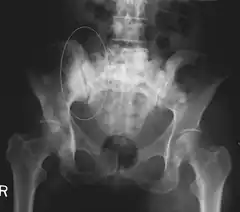

Sclerotic breast cancer metastases in the pelvis.

Skeletal Radiography

A plain film x-ray of the entire body can identify bone metastasis. However, the sclerotic or osteolytic lesions must be at least 1 cm in diameter.[14] A combination of X-ray, CT and MRI scans may be most sensitive in the diagnosis of cancerous bone metastasis.[14]